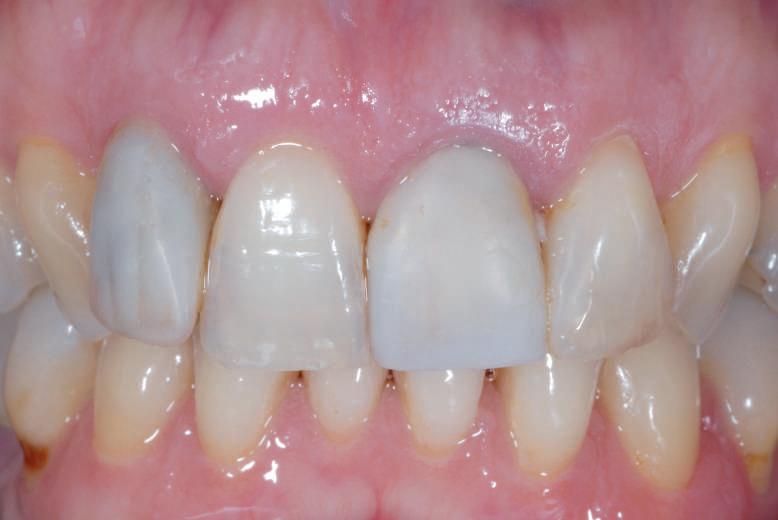

da tabagismo passando all’uso dei dispositivi a tabacco riscaldato. Successivamente rileviamo il colore, con spettrofotometro, e con scala-colori Vita e documentiamo fotograficamente la condizione clinica presente.

Il colore rilevato è A2. Sottoponiamo il paziente ad uno sbiancamento pro-

fessionale con un principio attivo PAP (acido ftalimidoperossicaproico) che presenta il vantaggio di non sollecitare la sensibilità, pur mantenendo l’aspettativa di un risultato efficace nell’ottenere la luminosità del sorriso. Lo sbiancante ad uso professionale BRILLIANT LUMINA (Coltene), risulta essere per l’operatore di facile applicazione: ven-

gono protette le gengive con la diga liquida fotopolimerizzata, e si mescola il gel sbiancante lasciando cadere nel vasetto contenente 2 ml di gel, 3 gocce di liquido attivatore. Si ottiene il gel sbiancante di una consistenza ideale per una applicazione sulle superfici dentali sicura e pratica durante l’apposizione. Vengono eseguiti 4 step da 15 minuti.

Dopo ogni step viene aspirato il gel, pulite le superfici dentali con del cotone idrofilo e si riappone nuovamente il gel. Al termine dei 4 step, si aspira, si asciuga e viene tolta la diga. Si rileva e si condivide con il paziente il risultato ottenuto, A1, e viene documentato fotograficamente. Il paziente appare gioioso del risultato è favorevolmente colpito di non aver sofferto durante il trattamento di sensibilità. Alla persona assistita sono stati programmati dei follow-up per il trattamento successivo delle white spots con applicazioni di resine infiltranti e rigenerazione guidata dello smalto.